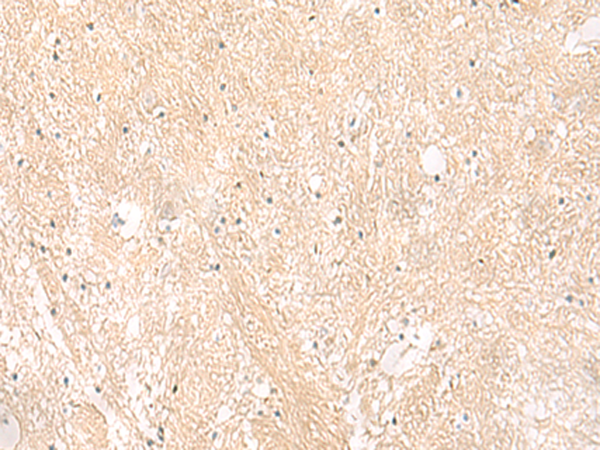

分类: 科研抗体货号: P02876别名: HC9; PSC9; HsT17706应用: WB,IHC反应种属: Human, Mouse, Rat